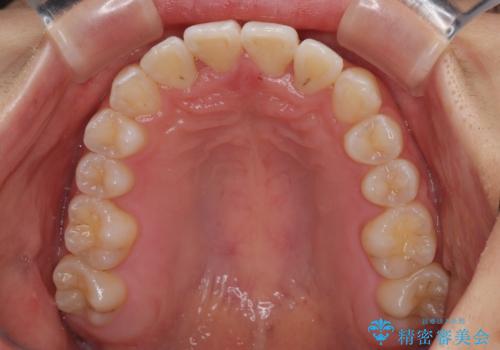

前歯のクロスバイト 裏側に隠れた歯をワイヤー装置で短期間治療

装置の外見を気にしていましたが、短期間で治療を終えることができるだろうと伝えると、安価であるメタルブラケットを選択されました。

想定通り、1年強で綺麗に仕上げることができました。